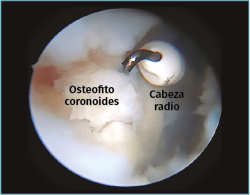

Método: hemos revisado 38 pacientes con codo rígido postraumático o degenerativo que se trataron mediante artrolisis artroscópica entre 2013 y 2016, con un seguimiento medio de 25 meses (38-15). Según la etiología de la rigidez, clasificamos a los pacientes en 2 grupos: grupo 1, los pacientes con rigidez por patología degenerativa del codo, y grupo 2, los pacientes con rigidez postraumática. Clasificamos la rigidez siguiendo la escala de Morrey y utilizamos la escala funcional Mayo Elbow Performance Index (MEPI), que evalúa el dolor, la movilidad, la estabilidad y la función del codo pre- y postoperatoriamente. Describimos los procedimientos artroscópicos realizados en cada paciente, que incluyen la sinovectomía, el desbridamiento de tejido fibroso, la capsulectomía anterior y/o posterior, la resección de osteofitos en la parte anterior y posterior del codo, la extirpación de cuerpos libres y la liberación “abierta” del nervio cubital.

Method: a review was performed on 38 patients with stiff elbow due to degenerative or post-traumatic reasons, and who were treated by arthroscopic arthrolysis between 2013 and 2016, with a mean follow-up of 25 months (38-15). Elbow stiffness was classified following the Morrey scale and the Mayo Elbow Performance Index (MEPI) functional scale was used to evaluate pain, mobility, stability and elbow function pre- and post-operatively. The arthroscopic procedures performed on each patient are described, including synovectomy, debridement of fibrous tissue, anterior and/or posterior capsulotomy, resection of osteophytes in the anterior and posterior part of the elbow, extirpation of loose bodies and open release of the ulnar nerve.